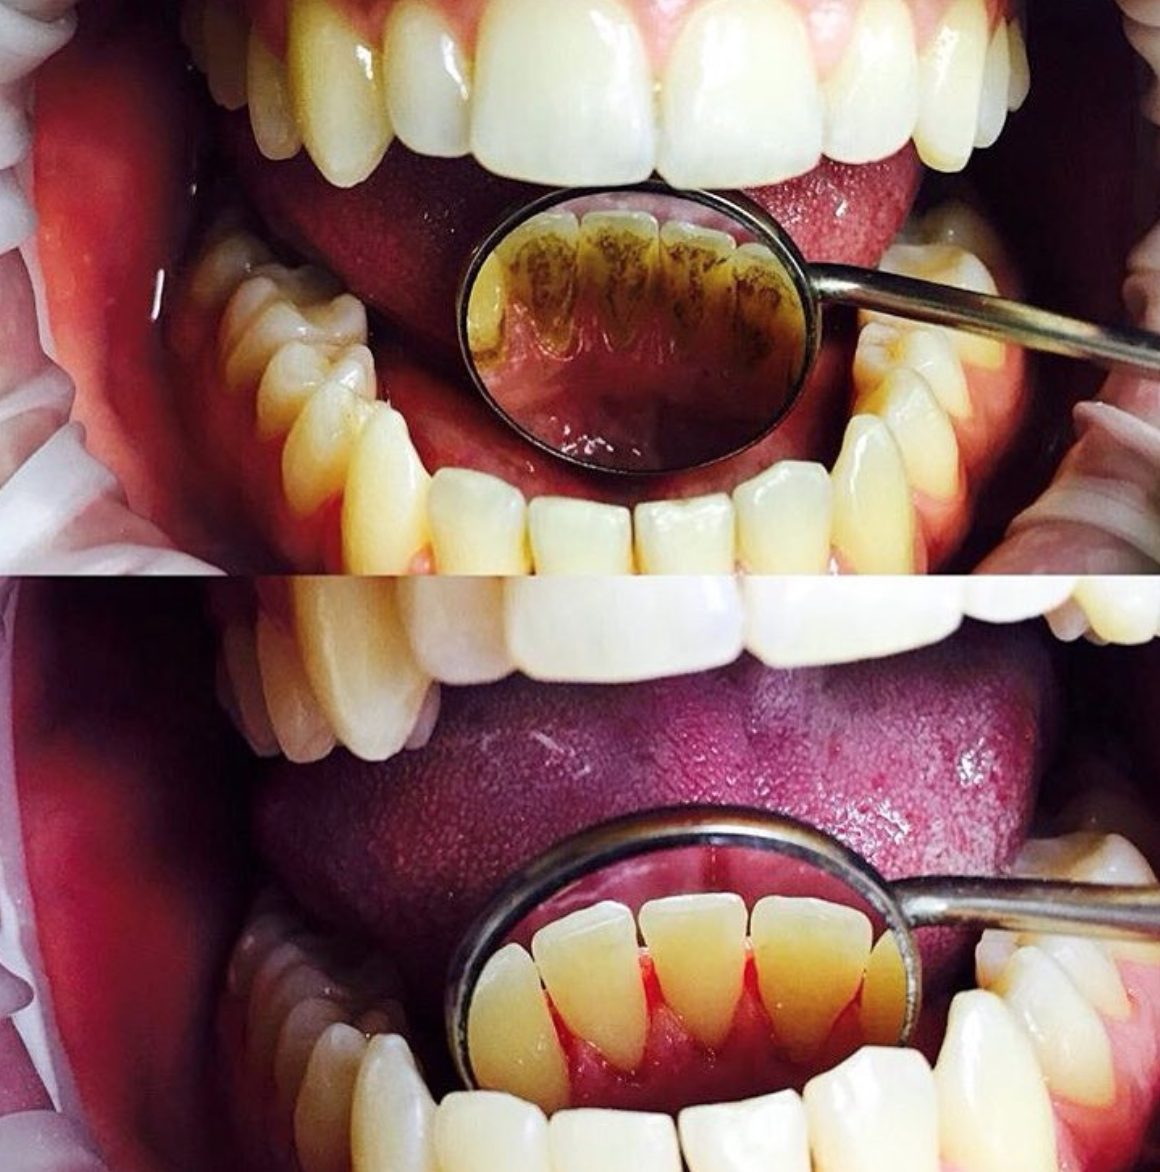

Убрать с эмали налёт и зубной камень

Снятие зубных отложений с помощью ультразвука

Твердые отложения (зубной камень) образуются в межзубных промежутках, на зубах в придесневой и поддесневой областях. Зубной камень может привести к развитию таких заболеваний, как гингивит, пародонтит или кариес. Процедуру проводят ультразвуковым скейлером, который с помощью вибраций удаляет твердые отложения с поверхности зуба.

Чистку делают с помощью ультразвукового скалера, который посылает вибрации на поверхность зуба. Такая технология безопасна и безболезненна. Это отличная альтернатива химическим или механическим способам снятия зубных отложений.